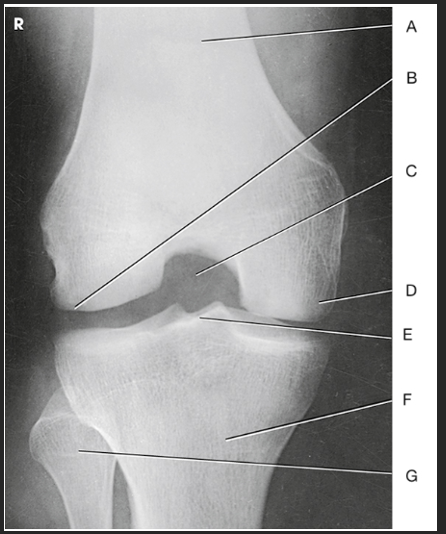

Label the image: A

popliteal surface

Label the image: B

adductor tubercle

Label the image: C

medial epicondyle

Label the image: D

medial condyle

Label the image: E

lateral condyle

Label the image: F

lateral epicondyle